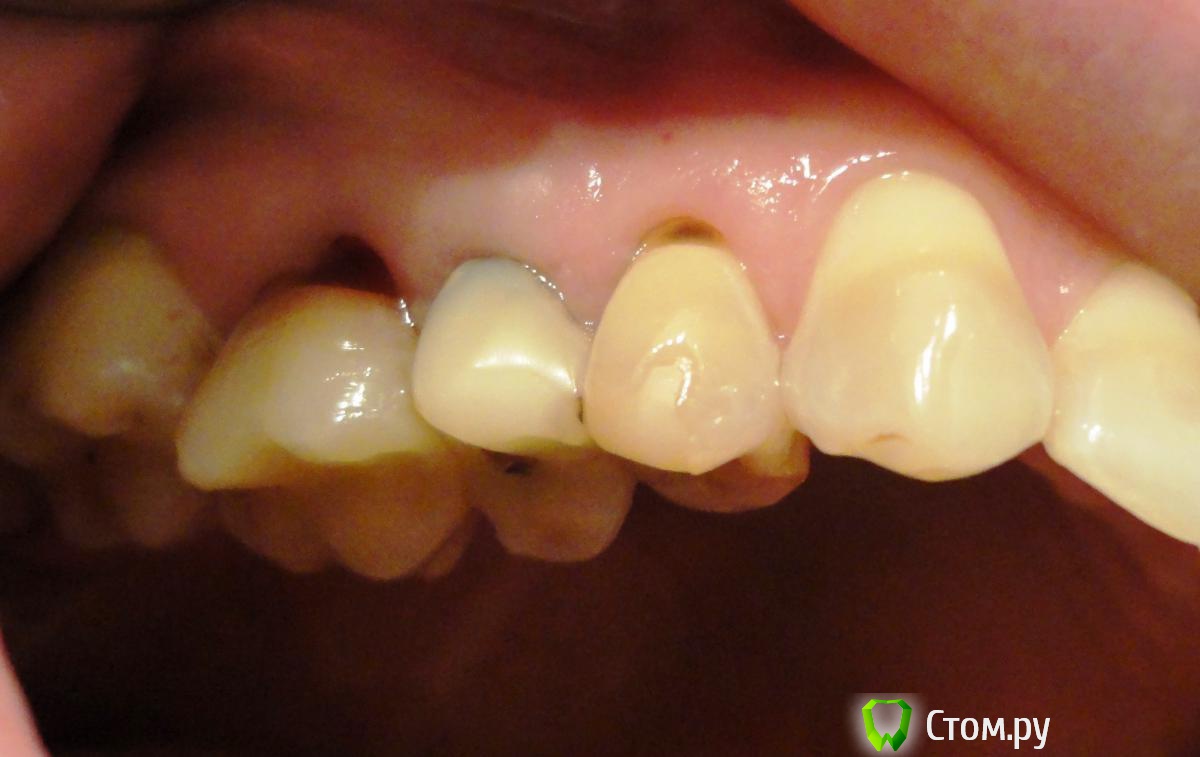

Необыкновенная Опубликовано 17 октября, 2014 Поделиться Опубликовано 17 октября, 2014 (изменено) Добрый день, уважаемые стоматологи!Прошу совета:Фото № 1 - рецессия десны на нижних зубах. Вопрос - что можно сделать? Что, в 2-х словах, представляет из себя методика / (операция) / варианты? Какова гарантия приживаемости? Надолго ли хватает? Фото № 2 - из-за той же рецессии и клиновидных дефектов, появилось оголение корней (конкретные на фото 4, 5, 6 - пойдут под коронки). У 6-ки корень красный (резорциновый вроде говорили?). Вопрос - т.к. после установки коронок будут видны корни из-за ушедшей десны, ВОЗМОЖНО ЛИ хирургически воссоздать нормальный десневой край и сосочки? Розовую керамическую десну не хочу ((Фото № 3 - ОПТГ - прилагаю на всякий случай, по кости вроде пока всё в норме. Или уже нет?(просьба не пугаться глубокой коричневой полосы на зубах, я не курю и посещаю гигиениста иногда )) - это тетрациклин, отбеливание не помогает (и больно). И просьба не пугаться скученности, ортодонтическое лечение было давно (всё вернулось), готовлюсь к протезированию. Спасибо всем заранее за рассмотрение вопроса и консультации!!! Изменено 17 октября, 2014 пользователем Необыкновенная Ссылка на комментарий

SDC Опубликовано 17 октября, 2014 Поделиться Опубликовано 17 октября, 2014 (изменено) Добрый день, уважаемые стоматологи!Прошу совета:Фото № 1 - рецессия десны на нижних зубах. Вопрос - что можно сделать? Что, в 2-х словах, представляет из себя методика / (операция) / варианты? Какова гарантия приживаемости? Надолго ли хватает? Фото № 2 - из-за той же рецессии и клиновидных дефектов, появилось оголение корней (конкретные на фото 4, 5, 6 - пойдут под коронки). У 6-ки корень красный (резорциновый вроде говорили?). Вопрос - т.к. после установки коронок будут видны корни из-за ушедшей десны, ВОЗМОЖНО ЛИ хирургически воссоздать нормальный десневой край и сосочки? Розовую керамическую десну не хочу ((Фото № 3 - ОПТГ - прилагаю на всякий случай, по кости вроде пока всё в норме. Или уже нет?(просьба не пугаться глубокой коричневой полосы на зубах, я не курю и посещаю гигиениста иногда )) - это тетрациклин, отбеливание не помогает (и больно). И просьба не пугаться скученности, ортодонтическое лечение было давно (всё вернулось), готовлюсь к протезированию. Спасибо всем заранее за рассмотрение вопроса и консультации!!!Фото № 1 Возможно закрыть множественные рецессии десны, желательно ортодонтическое лечение. В 2-х словах :подтяжка десны с утолщением биотипа за счет трансплантации слизисто-десневого трансплантата с неба. Хватает надолго. Гарантия - это означает, что доктор или клиника берет на себя обязательства по устранению осложнений и/или проведение повторной операции без доп. оплаты. Гарантировать реакцию Вашего организма доктор не может. Фото №2 нет необходимости в закрытии рецессии. Просто коронки на 4, 5, 6-й зубы. Межзубные сосочки в норме. Обнажение корней на 6-м зубе произошло за счет его выдвижения в сторону дефекта з. ряда на н.ч. На 4-м - дефект твердых тканей в пришеечной области скорее всего из-за перегрузки Фото № 3 С костной тканью в области зубов относительный порядок, есть необходимость в восстановлении непрерывности зубных рядов с применением имплантации. Изменено 17 октября, 2014 пользователем SDC Ссылка на комментарий